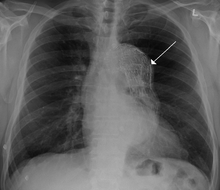

| Thoracic aortic aneurysm with arrow marking the lateral border of the aorta. | |

A thoracic aortic aneurysm is an aortic aneurysm that presents primarily in the thorax.

A thoracic aortic aneurysm is the "ballooning" of the upper aspect of the aorta, above the diaphragm. Untreated or unrecognized they can be fatal due to dissection or "popping" of the aneurysm leading to nearly instant death. Thoracic aneurysms are less common than an abdominal aortic aneurysm.[1] However, a syphilitic aneurysm is more likely to be a thoracic aortic aneurysm than an abdominal aortic aneurysm.